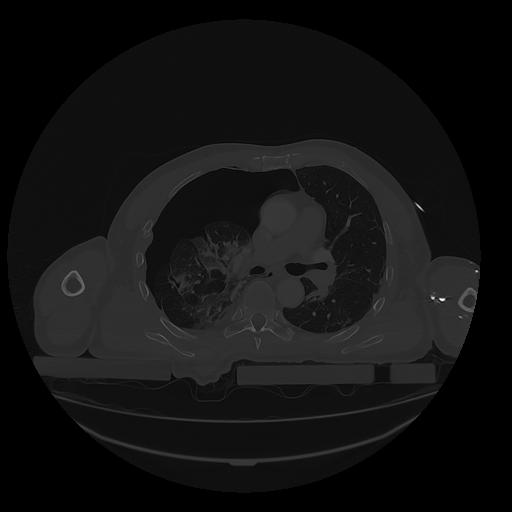

31 PULMON,CE,Vol,1.0,PULMON,,